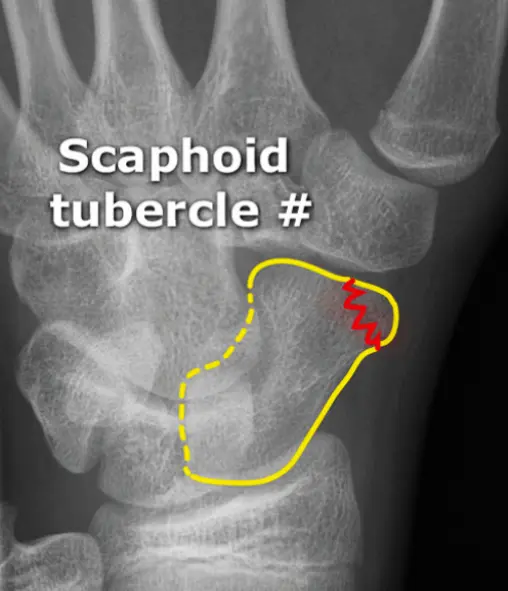

Follow the Cortex

- x-ray of wrist undisplaced fracture of scaphoid

- In Trauma â âFollow the Cortexâ â adjust brightness/contrast to reveal the fracture line.

A 29âyearâold man fell from a ladder and presents with pain in the wrist.

- Site â wrist

- Type â (Specify fracture type)

- Fracture line â (Describe orientation)

- Displacements â (Note any displacement)

- Special issues â (Highlight any neurovascular or softâtissue concerns)

A 37-year old man fell from a down the stairs, C/O pain at wrist ⢠Site ⢠Type ⢠Fracture line

- Displacements

- Special issues

- Site

- Type

- Fracture line

- ⢠Site

- ⢠Type

- ⢠Fracture line

- ⢠Displacements

- ⢠Special issues